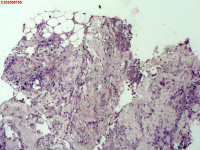

| 图片: | |

- 右侧胸壁穿刺组织活检

| 性别 | 女 | 年龄 | 81岁 | 临床诊断 | 胸锁关节结核? |

| 一般病史 | 胸部CT示:右肺下叶小结节,建议3-6个月复查,必要时胸外科会诊。左肺上叶多发小斑点、结节影,结核可能。右肺上叶多发点状影。双肺间质性改变。纵隔淋巴结肿大、钙化。右侧胸锁关节见骨质破坏,周围见软组织肿胀。 | ||||

| 标本名称 | 右侧胸壁穿刺组织活检 | ||||

| 大体所见 | B超:体表包块彩超示右侧胸壁混合回声包块,右侧胸壁低回声区,CDFI示:其内未见明显血流信号。 | ||||